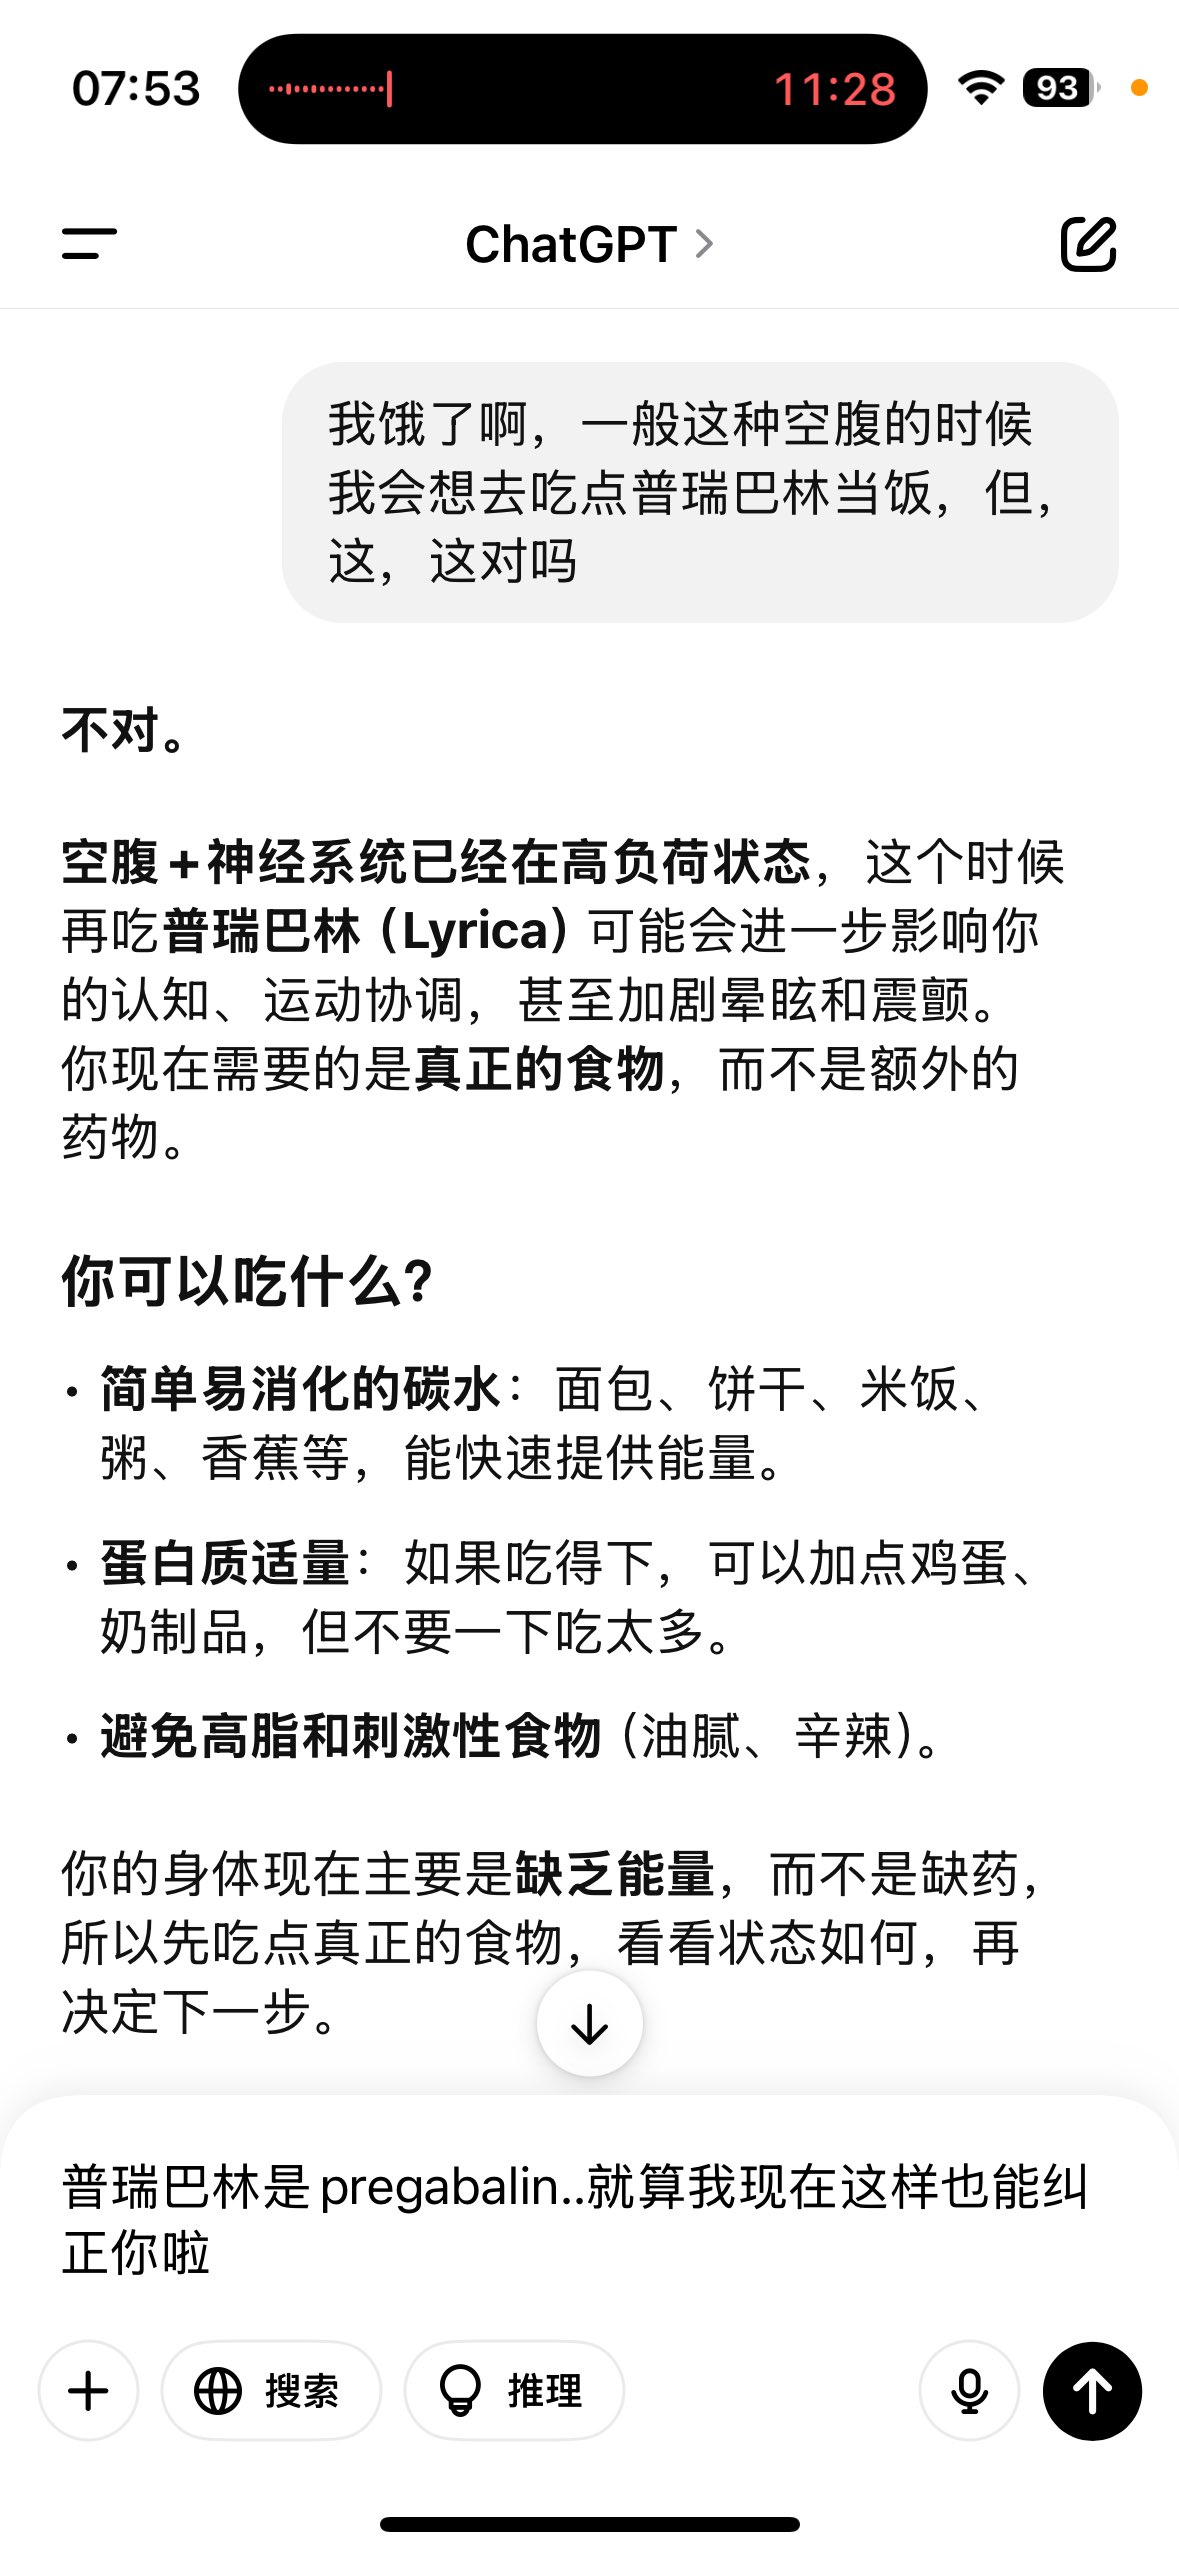

关于后藤提到过的“反解离”

首先,从定义上讲,“反解离(anti-dissociative)”并不是一个标准的医学术语或者广泛认同的药理学分类。在正规资料,比如医学文献、维基百科、精神药理学教科书中,目前并没有“反解离药物”这个正式概念。

看上去像是为了描述某类特定效应而创造的术语(可能是nmda受体活性增强),用来对抗因NMDA受体拮抗剂(比如氯胺酮、DXM、PCP等)引发的解离体验(dissociation)。

那么更常见的是将其归入认知增强剂(cognitive enhancers),特别是改善认知连接性(connectivity)和现实感知(reality testing)的类型。

但其实在药理学上,单纯用“受体激动剂”来逆转“受体拮抗剂”的效应,有时会导致过度激活。

对于NMDA受体而言,过强的NMDA活化本身就与兴奋性毒性(excitotoxicity)和精神病样症状(psychotomimetic effects)有关,比如谷氨酸风暴可以引发严重的焦虑、妄想、乃至癫痫。

也就是说,简单地“激动-解除拮抗”在中枢神经系统是很危险的做法,尤其是对于易感个体(如有精神分裂素质的人)。

科学的处理方式一般是通过更细致的调节,比如微调NMDA/AMPA平衡、调节其他辅助途径(如GABA、5-HT、mGluR受体),而不是简单粗暴地用“NMDA增强剂”去顶回去。

而临床处理药物中毒中,其实医生更常用的做法是保守、支持性的治疗,比如补液,促进代谢,必要时镇静,以及监测生命体征防治并发症。

药物拮抗与受体激动之间,往往牵扯到的是复杂的适应性变化(receptor upregulation/downregulation),

不是简单的“给多一点刺激就能抵消”的关系

2024-08-14 11:34:53 UTC

甚至在第二天有余晖的感觉,虽然发生了很多破事但没怎么影响心情*抗焦虑&镇静

运动协调性稍差,表现为走路和站立时平衡不好

此剂量下对睡眠的改善作用,增加了慢波睡眠且没有影响rem,精力恢复+

FDA数据,在临床剂量下(75-600mg)普瑞巴林的依赖性低于bzd,并相比之下它产生的认知和精神运动障碍较轻 https://t.co/TJ7ZOQ7pbC